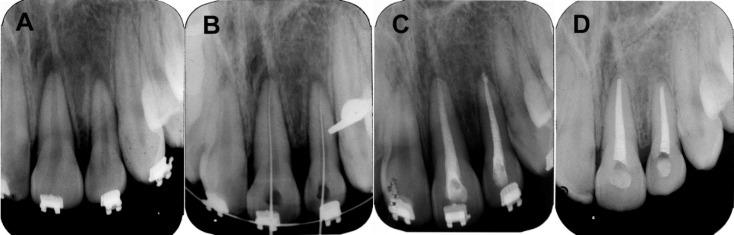

Accurate diagnosis, immediate care and proper treatment planning are important factors for the successful treatment of dental traumatic injuries. In extrusive luxation, postponement in treatment may lead to the need for new strategies for the resolution of unwanted consequences. The present case report describes an unusual condition of delayed treatment regarding extrusive luxation of two anterior teeth treated by intentional replantation. An 18-year-old female patient attended the Dental School for the treatment of a traumatic injury to the anterior teeth 5 days after a fall from a bicycle. Clinically, teeth #21 and #22 were extruded in incisal edges for 5 mm from their neighboring teeth, had edematous gingiva, showed grade II mobility and were painful to percussion. Radiographically, the roots were intact and the periodontal ligament space was thickened along its entire length. As immediate repositioning could not be performed, intentional replantation was recommended. After detaching the periodontal ligament, the teeth were extracted and the alveolus was curetted and irrigated with saline solution to remove the already-formed clot. After replantation, the teeth were restrained and the patient was medicated with antibiotics as well as analgesics. After 10 days, the splint was removed, the root canals were instrumented and then, filled with calcium hydroxide. After 30 days, they were completely obturated using gutta-percha. The 5-year follow-up showed root integrity, absence of mobility and normal periodontium. The outcomes of the current case report revealed that when intentional replantation was properly conducted, it could be considered an option for the treatment of extrusive luxation where the teeth were not to be immediately repositioned.

准确的诊断、及时的护理和恰当的治疗计划是成功治疗牙外伤的重要因素。在牙齿脱出性脱位中,治疗延迟可能导致需要采取新策略来解决不良后果。本病例报告描述了一例通过有意再植治疗两颗前牙脱出性脱位的延迟治疗的特殊情况。一名18岁女性患者在从自行车上摔下5天后到牙科学院治疗前牙外伤。临床检查发现,21号和22号牙切缘相对于邻牙脱出5毫米,牙龈水肿,Ⅱ度松动,叩诊疼痛。影像学检查显示,牙根完整,牙周膜间隙在全长范围内增宽。由于无法立即进行复位,建议采用有意再植。分离牙周膜后,拔除患牙,刮除牙槽窝并用生理盐水冲洗以清除已形成的血凝块。再植后,固定患牙,并给予患者抗生素和镇痛药。10天后,拆除夹板,预备根管,然后用氢氧化钙充填。30天后,用牙胶尖进行根管完全充填。5年随访显示牙根完整,无松动,牙周组织正常。本病例报告的结果表明,当正确进行有意再植时,对于不能立即复位的脱出性脱位牙,可将其视为一种治疗选择。